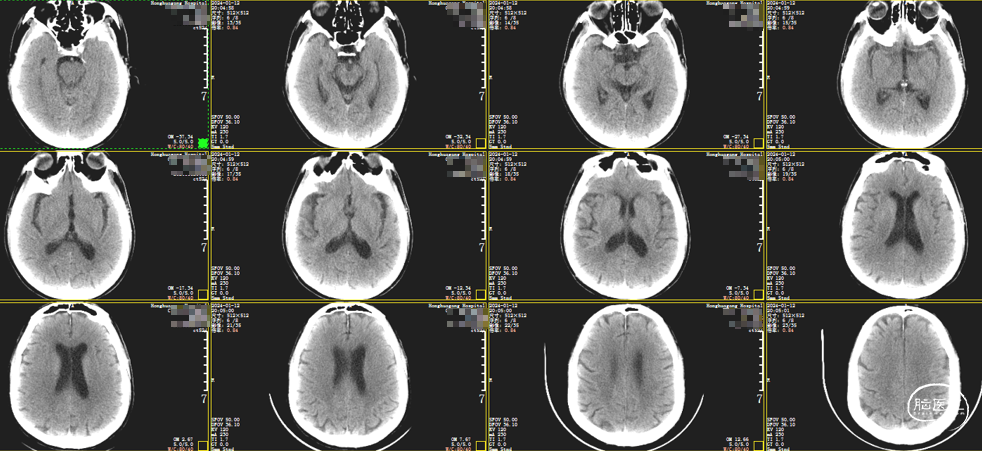

头颅CT :未见出血及梗死。

薄层CT:右侧大脑中动脉走形区可疑高密征。

后复查CT